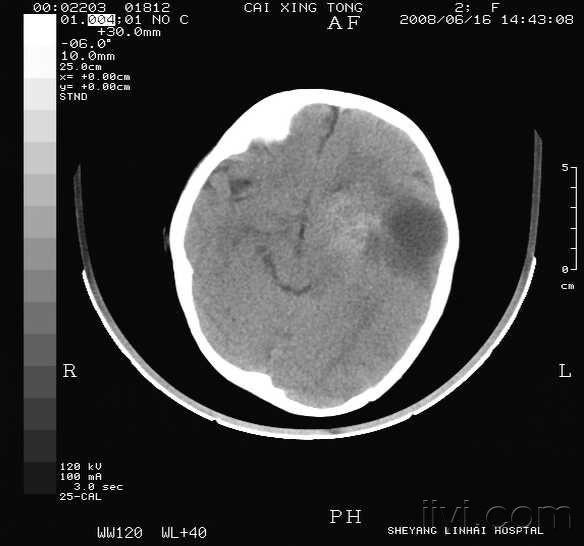

“老先生,您把项链取下来再做CT”“你看是不是弹片”这张图片是82岁吴以先老人的CT照,当初拍片时,医生说,“老先生,您要把项链取下来再做CT。”吴以先说,“我从来没戴过项链,你看会不会是弹片?”由此,引出了老人一段不平凡的往事。20年前,吴以先做CT检查时,由于颈部有许多弹片,医生误将弹片认作是他戴的项链,于是提醒他要把项...